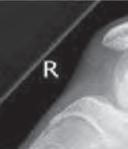

Przebieg szczeliny złamania: A – złamanie poprzeczne (RTG, widok z przodu); B – złamanie skośne (RTG, widok z przodu i z boku); C – złamanie spiralne (RTG, widok z przodu i z boku); D – złamanie w kształcie motyla (RTG, widok z boku); E – złamanie wieloodłamowe (RTG, widok z przodu i z boku).